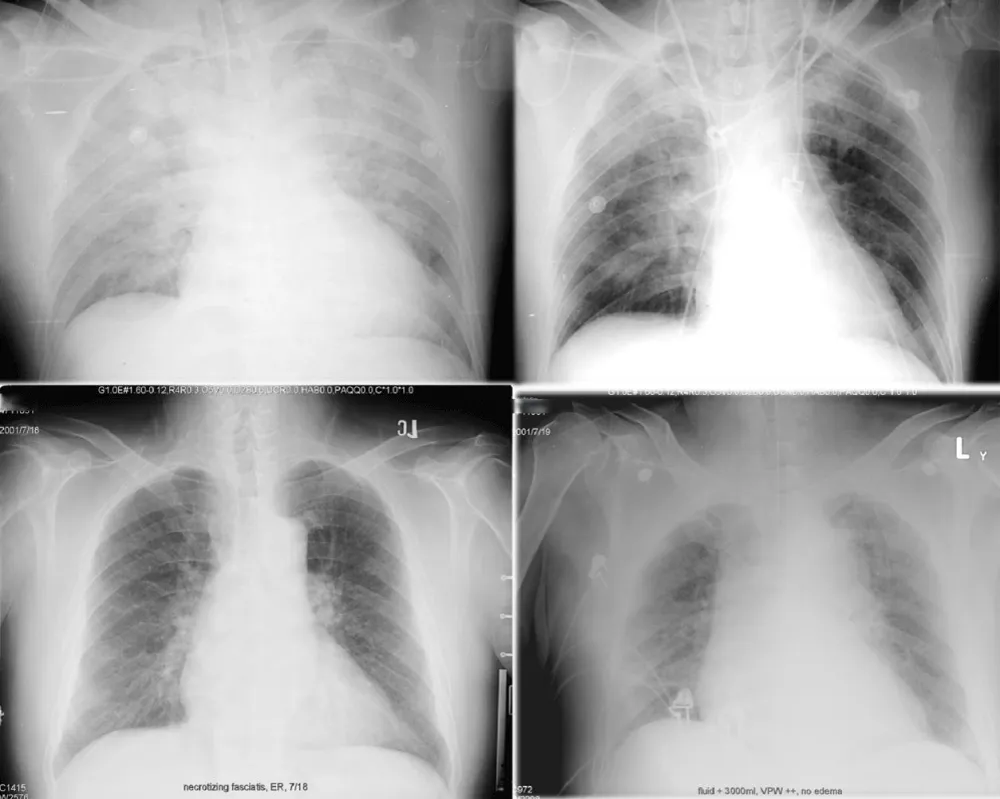

The lung transparency index (LTI) summarizes normalized per‑pixel intensity within lung masks (0–1); lower values indicate edema‑like opacity and redistribution. In Figure 2, we illustrate how VPW and lung transparency co‑vary with fluid balance and volume overload.

Figure 2: Radiographic examples of fluid balance and overload. Top row (same patient): left, input/output +1000 mL; right, I/O −1000 mL. Bottom row (different patient, necrotizing fasciitis with fluid overload): widened VPW and reduced lung transparency consistent with congestion.